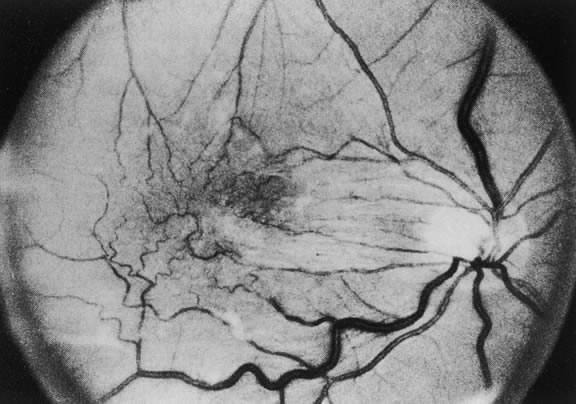

The posterior vitreous surface is more easily identified in diabetes. Adjacent to neovascularization it is thickened, presumably because of cellular proliferation. In other areas, it has a glistening, taut appearance. The presence of vitreous hemorrhage often provides clues to the status of vitreous. After partial vitreous detachment, blood may layer out and define the anterior extent of an inferior detachment with a characteristic boat-shaped hemorrhage, or blood may layer on the posterior vitreous surface after a partial superior detachment (Fig. 23).

Fig. 23. Vitreous detachment in proliferative diabetic retinopathy. a. blood deposited on the detached posterior surface of the formed vitreous after hemorrhage into the posterior fluid vitreous; b. neovascular and fibrous proliferations creating a tight vitreoretinal adhesion, which pulls the retina forward and holds the formed vitreous posteriorly; c. localized collection of subretinal fluid; d. curved upper surface of a “mushroom” of formed vitreous extending posteriorly to the retina through a “hole” in the posterior vitreous surface; e. hole in the posterior vitreous surface; f. blood collected in the dependent portion of the mushroom of vitreous after hemorrhage into the formed vitreous; g. posterior vitreous surface; h. a single new vessel stretching between the retina and proliferations on the detached posterior vitreous surface without traction retinal detachment; i. blood pooling between the retina nd the posterior vitreous surface at the inferior limit of vitreous detachment after hemorrhage into the posterior fluid vitreous; j. blood settled out in the inferior part of the formed vitreous. (Davis MD: Natural course of diabetic retinopathy. In Kimura SJ, Caygill WM [eds]: Vascular Complications of Diabetes Mellitus. St Louis, CV Mosby, 1967)